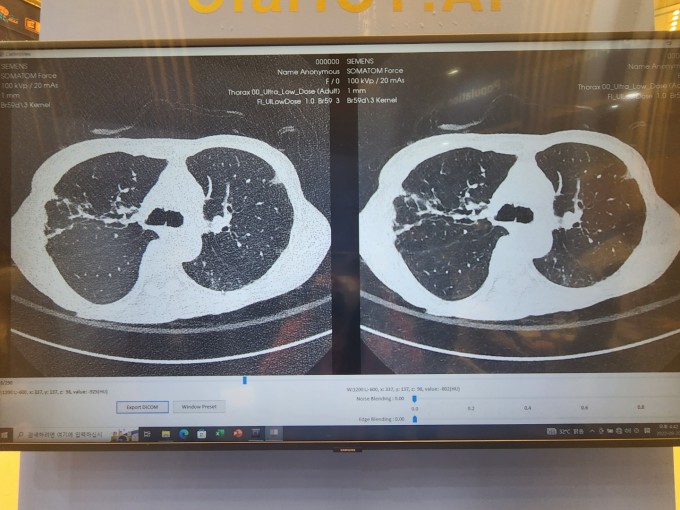

복부 CT는 X-선을 이용하여 환자의 복부를 다양한 각도에서 촬영하고, 이 정보를 컴퓨터로 처리하여 단층 이미지를 생성하는 방식으로 작동합니다. CT 촬영 과정은 주로 다음과 같은 단계로 이루어집니다:

- 촬영 진행: 환자는 CT 장비의 테이블에 누워 있으며, 장비가 환자의 복부를 여러 방향에서 스캔합니다. 이 과정은 수십 초에서 몇 분 사이에 완료됩니다.

- 영상 분석: 생성된 단층 이미지는 방사선과 전문의에 의해 분석되며, 필요한 경우 추가 영상 촬영이나 다른 진단 방법이 권장될 수 있습니다.